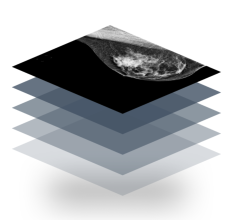

Despite decades of progress in breast imaging, one challenge continues to test even the most skilled radiologists ...

According to a study published in Radiology, a journal of the Radiological Society of North America, the newer, 3D form ...